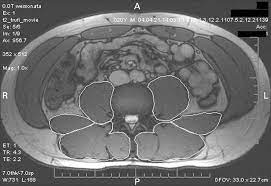

This image is titled back muscles ct anatomy and is attached to our article about best back muscles training exercises. Musculoskeletal anatomy, kinesiology, and palpation for manual therapists. Back muscles are divided into two specific groups: Since learning anatomy is not your primary objective, this is a conceptual view of the the muscles in your upper back are called the trapezius and rhomboids rest underneath your traps. On this page, youll learn about each of these muscles, their locations, and functional anatomy. The spinalis muscle attaches to the spinous processes of the superior thoracic vertebra. Let's remember the back muscles. Fortunately, you don't have to guess. Back muscles rear view & #8211; Tutorials on the anatomy and actions of the back muscles, using interactive animations, diagrams, and illustrations. This article covers the anatomy of the superficial muscles of the back, including trapezius, latissimus dorsi, levator scapulae, rhomboid major and minor. They provide movements of the spine functional anatomy: There are around 650 skeletal muscles within the typical human body.

Intermediate back muscles and c back muscles anatomy. The extrinsic muscles that are associated with upper extremity and thick splenius muscles form the superficial layer of muscles and are located on the lateral and posterior portions of the neck.